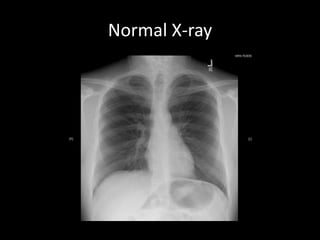

Normal X-ray